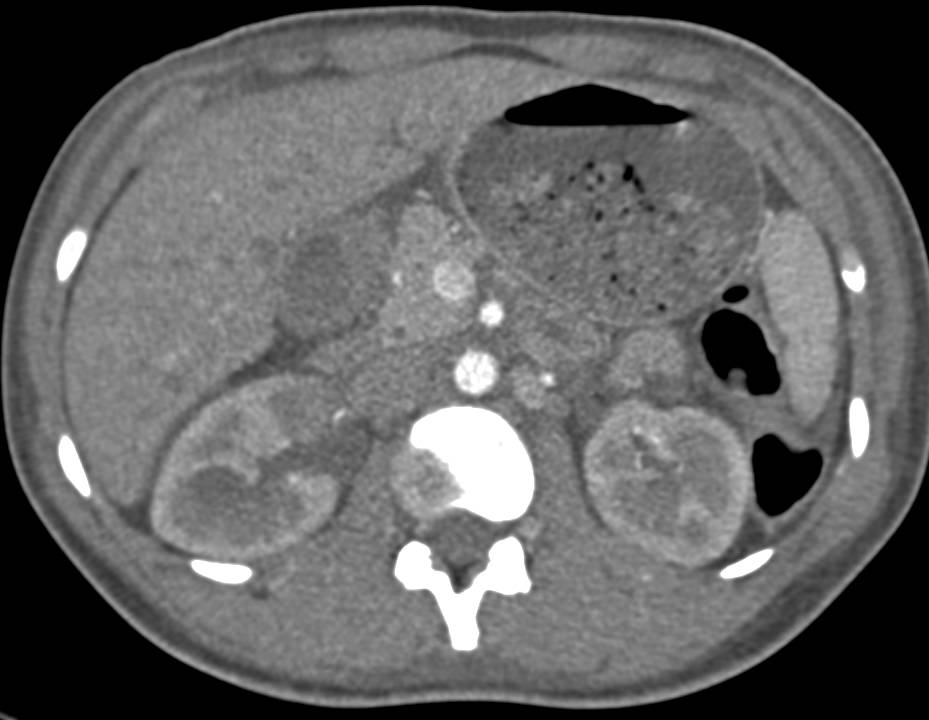

Renal Cell Carcinoma Presents as a Spontaneous Renal Bleed